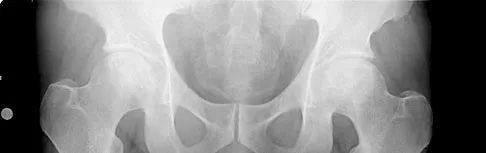

Which of the following is considered the best cementless acetabular reconstruction method when planning for total hip arthroplasty in a patient with developmental dysplasia of the hip (DDH)?

Explanation